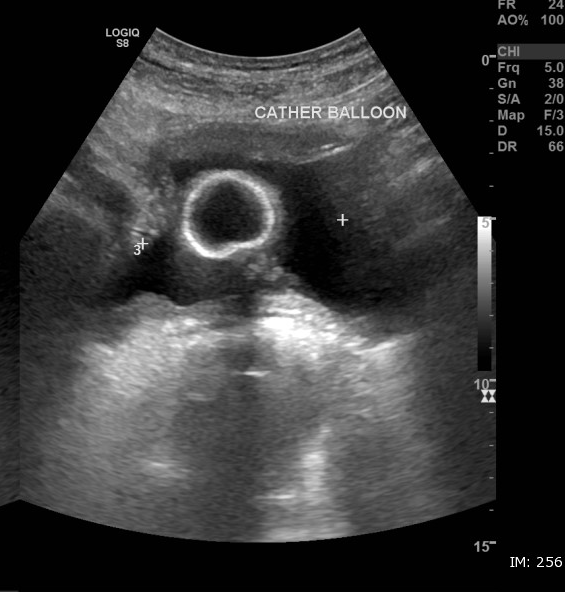

Vérifier la présence d’une SAD

Chez un patient déjà sondé ou après pose récente :

-

Rechercher dans la vessie une image ronde, anéchogène ou hypoéchogène, correspondant au ballonnet de la sonde.

Vérifier que le ballonnet est bien intra-vésical et non dans l’urètre.

La persistance d’une vessie distendue malgré la présence du ballonnet évoque :

obstruction de la sonde,

ballonnet mal positionné,

caillot ou rétention sous sonde.

➡️ Évite les faux diagnostics de globe et les sondages inefficaces.